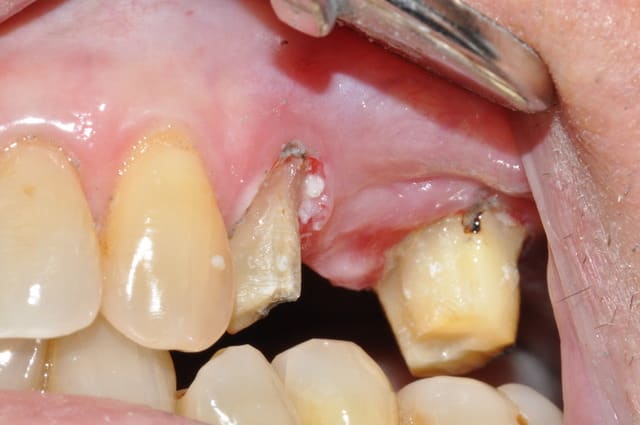

patiente envoyée pour ex° de 26 par un neurologue

souffre depuis 18mois, le bridge à 2ans

Déjà, les couronnes me paraissent bien débordantes

Deuxièmement, je ne vois pas de traitement canalaire sur ces dents. Peut etre souffrent elles de pulpite chronique

patiente revue ce matin

depose du bridge existant sous AL

et empreinte pour provisoire résine en sous occlusion

premiere réaction de la patiente bridge déposé

"çà ma change mes dents de devant, je mords plus pareil"